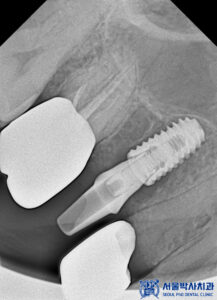

임플란트 식립 전에는 CT 촬영을 통해

뼈의 두께와 높이,

신경과의 거리 등을

정밀하게 확인했습니다.

CT 결과를 바탕으로 식립 각도와

깊이를 세밀하게 계획하고,

충분한 뼈 지지가 확보될 수 있도록

맞춤형 임플란트 계획을 수립하였습니다.

임플란트의 치유 기간이 충분히 지난 뒤,

보철 작업을 진행했습니다.

정밀한 교합과 잇몸 라인을 구현하기 위해

맞춤형 지대주를 제작하고,

이에 맞는 보철물을 장착하였습니다.